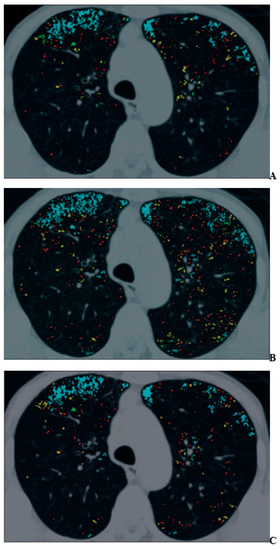

For COPD assessments, CT can be used to assess morphological and functional changes related to COPD [48,49,50,51,52,53,54,55,56,57,58,59,60]. During the last few decades, many commercially available and proprietary software products as well as various visual scoring systems have been used for the CT-based assessment of COPD, with two major approaches reported in the literature for quantitative CT assessment of COPD [48,49,50,51,52,53,54,55,56,57,58,59,60]. One is the determination of the percentage of low attenuation area (%LAA) in the lung, which indicates emphysema changes, and the other is the determination of the wall area ratio (WA%) of the bronchi, which indicates bronchial lumen narrowing and bronchial wall thickening [48,49,50,51,52,53,54,55,56,57,58,59,60]. In the past literature [48,49,50,51,52,53,54,55,56,57,58,59,60], it has been suggested that the %LAA has a good correlation with FEV1/FVC, %FEV1, %DLCO, or DLCO/VA and that the WA% also has a good correlation with FEV1/FVC and %FEV1. Therefore, it is suggested that these imaging parameters are useful as quantitative imaging biomarkers for COPD [48,49,50,51,52,53,54,55,56,57,58,59,60]. In addition, three-dimensional (3D) airway luminal volumetry has been introduced as another quantitative method for evaluating the airways of COPD patients [58,59]. Taking the findings provided by these quantitative CT assessments of COPD and the need for radiation dose reduction strategies into consideration [42,43,44,45,46,58,59,60], the application of IR algorithms has been considered an important issue for an accurate quantitative CT evaluation of COPD. One study demonstrated that agreement for the %LAA between standard-dose CT obtained at 300 mA and reduced-dose CT at 50 mA tended to improve when using AIDR 3D rather than conventionally applied FBP [44] (Figure 1).

Figure 1.

A 70-year-old man with mild pulmonary emphysema (permission from reference [44]). (A–C) Images show low-attenuation lung regions with standard-dose CT (A), low-dose CT without adaptive iterative dose reduction using 3D processing (B), and low-dose CT with adaptive iterative dose reduction using 3D processing (C). Color coding of low-attenuation lung regions is as follows: class 1, red; class 2, yellow; class 3, green; and class 4, cyan.

Moreover, the ACTIve study group applied the same hybrid-type IR algorithm and obtained similar results for standard-dose CT at 240 mA and reduced-dose CTs at 120 mA and 60 mA [60]. Thus, the use of a hybrid-type IR resulted in greater consistency of emphysema quantifications performed on reduced-dose and ultra-low-dose CTs than on standard-dose CT images. Although the %LAA and the WA% have been recommended as the two main quantitative parameters for COPD assessment [41,42,43,44,45,46,47,48,49,50,51,52,53,54,55,56,57,58,59,60], 3D airway luminal volumetry has also been introduced as another method for quantitative ADCT evaluation of airflow limitation in COPD [58,59]. Koyama et al. assessed the utility of a hybrid-type IR algorithm for quantitative bronchial assessment on reduced-dose CT for patients with and without COPD and provided evidence of a significant correlation of WA% and the airway luminal volume percentage from the main bronchus to the peripheral bronchi (LV%) between standard- and reduced-dose CT [58]. Moreover, LV% agreement between standard-dose and reduced-dose CTs can improve AIDR 3D in comparison with FBP [59]. Therefore, AIDR 3D can be recommended for quantitative COPD evaluation on ADCT in routine clinical practice.